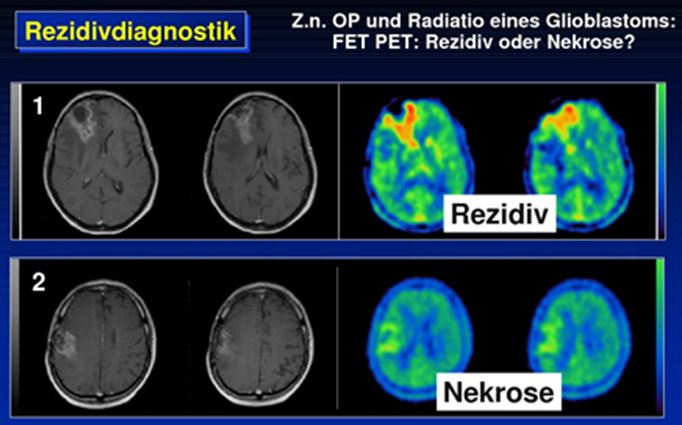

- F18-FET zur Darstellung von Hirntumoren

- Hirntumordiagnostik mit -FET(Fluoroethyltyrosin): Am häufigsten wird eine PET-CT-Untersuchung mit -FET eingesetzt, wenn der MRT-Befund im Re-Staging unklar ist. Durch die PET-CT wird ermöglicht, sicher zwischen Narbengewebe und einem Rezidiv zu unterscheiden.